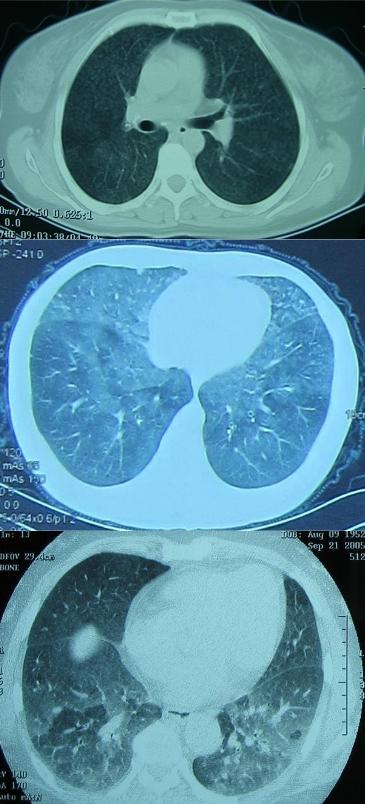

影像资料如下:

2012-2-16,在当地诊断为间质性肺炎;2012-3-29,病灶吸收;2013年10月,病灶较前明显吸收;2015-5-22,病灶加重;2015-5-29(一个星期后)病灶又有所吸收。

后来,患者到中日医院就诊,这是2015-9-30在中日医院的胸部CT(右)与2015-8-20胸部CT(左)有进一步吸收的对比: